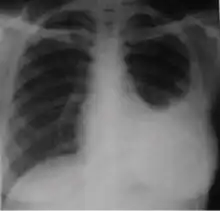

Chest x-ray showing dense opacity pleural effusion in the lower left lung of primary pulmonary TB.